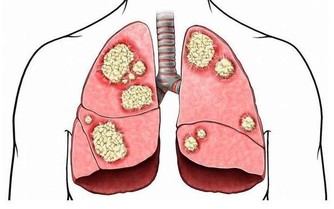

5.海帶血液淨化劑

海帶不但是含碘較高的食物,還富含豐厚的膳食纖維和膠質,其間的膠質成分能聯繫血液中的有害物質,如重金屬,具有排毒、淨化血液的效果。

6.納豆血栓溶解劑

納豆是由黃豆經過納豆菌發酵製成的豆製品,研討證明,納豆中的納豆激酶能“溶解”血栓,避免心肌梗死、腦梗死等疾病。

此外,納豆還富含大豆異黃酮、鋅、鈣與維生素K,不但能彌補雌激素,改善更年期症狀,還能夠防止骨質疏鬆。